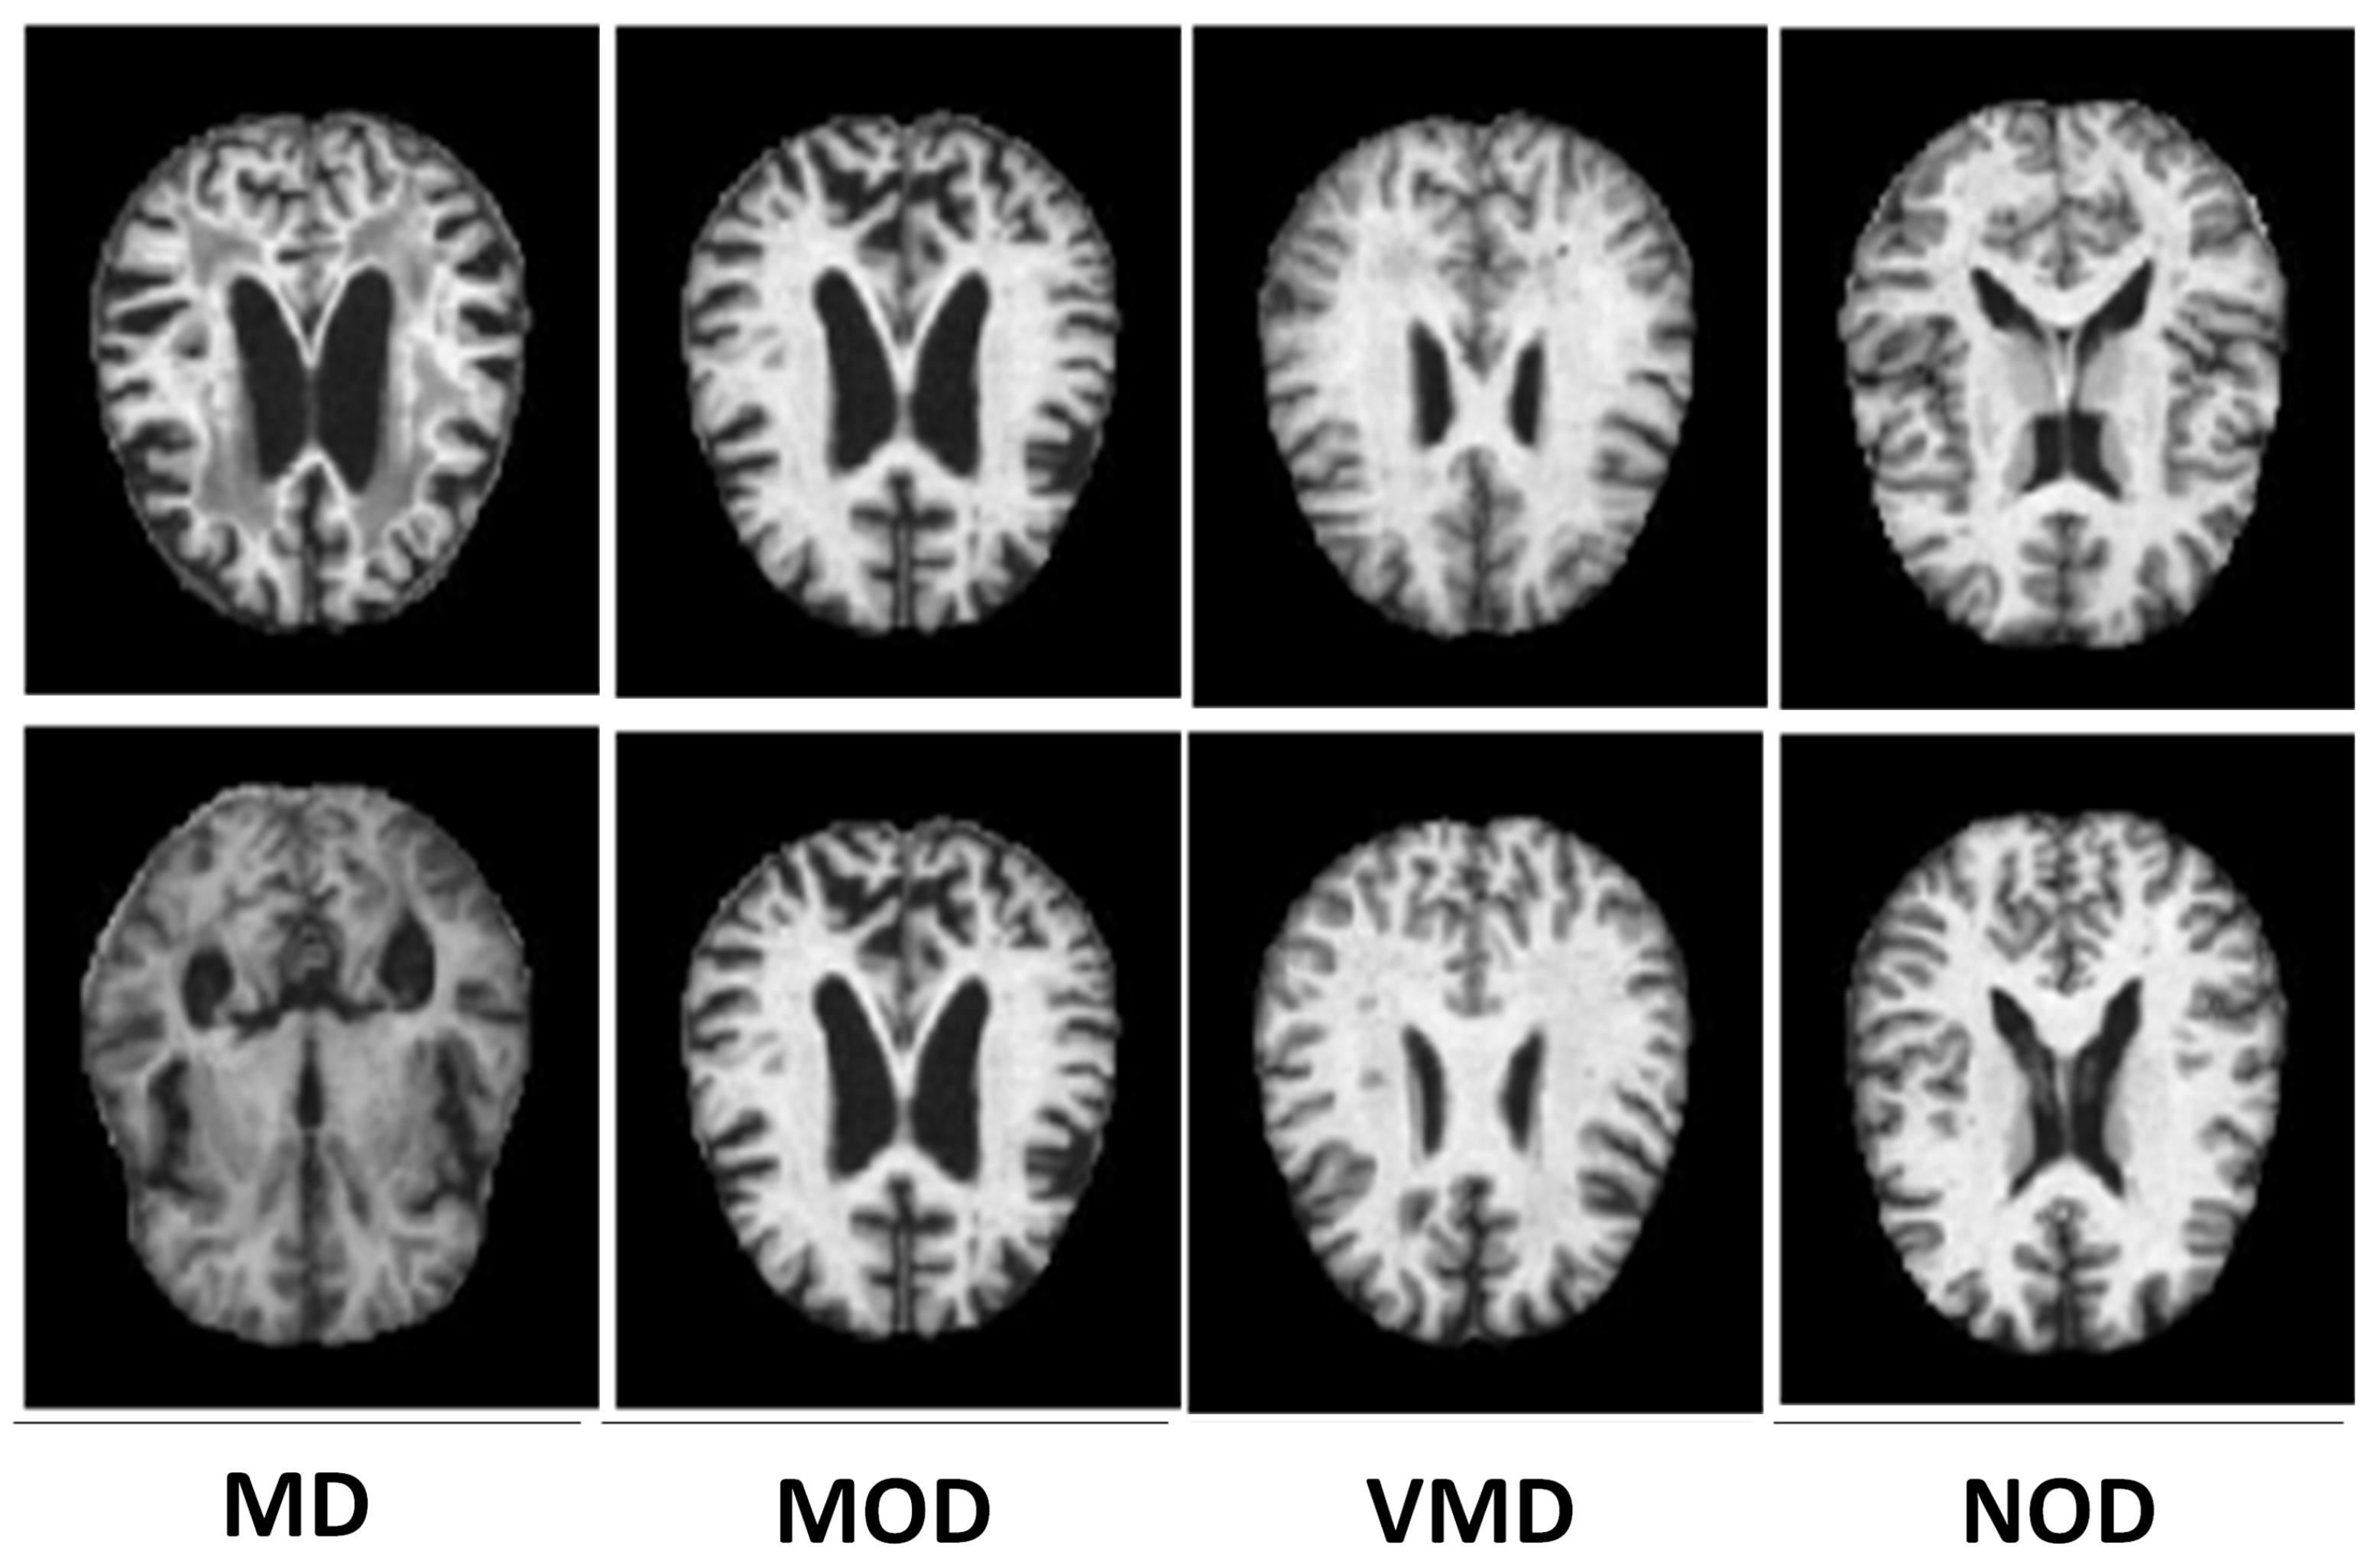

3.1. Description of the AD Dataset